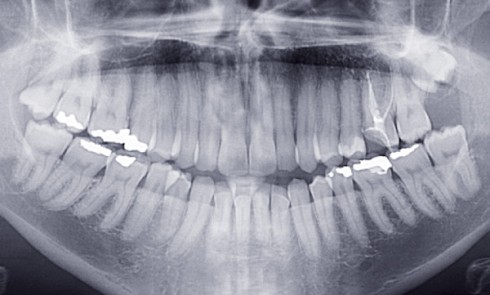

Présentation du cas Il s’agit d’un patient adulte de 28 ans (fig. 1) présentant une classe I, une dysharmonie dento-maxillaire (DDM),...